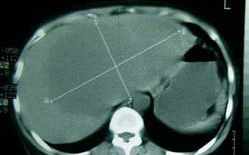

3.靜脈腎盂造影(ivp)能顯示囊腫壓迫腎實質的程度,並可與腎積水相鑑別。

CT,對B超檢查不能確定者有價值,囊腫伴出血、感染、惡變時,呈現不均質性,CT值增加,當CT顯示為囊腫特徵時,可不必再作囊腫穿刺。